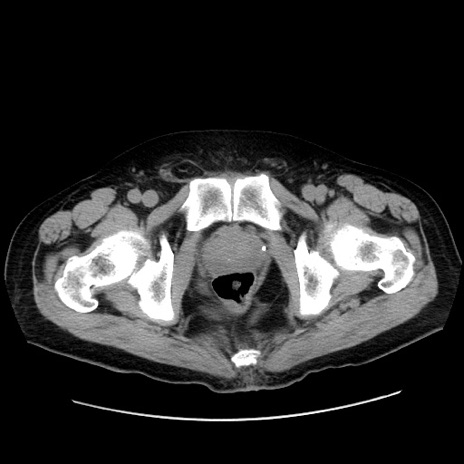

症例30(横断像)

【症例】80歳代男性

【主訴】臍周囲痛

【現病歴】約6時間前から臍下部痛が出現。次第に腹部膨隆・背部痛も生じてきたため来院。背部痛の場所は変化しない。

【身体所見】意識清明、BT 36.3℃、BP  131/87mmHg、P 87bpm、SpO2 100%(RA)、臍周囲自発痛・圧痛あり、反跳痛なし、自発痛部位に一致して板状硬あり、腹部膨隆、腸雑音減弱、CVA tenderness両側陰性。

【データ】WBC 19600、CRP 0.33